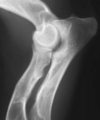

3.5m Yorkie

lateral humeral condylar fracture

Incomplete ossification imaging description

l radiolucent line up to 1 mm wide, extending proximally from the trochlear articular sur face to the physeal scar or supratrochlear foramen (50% cases)